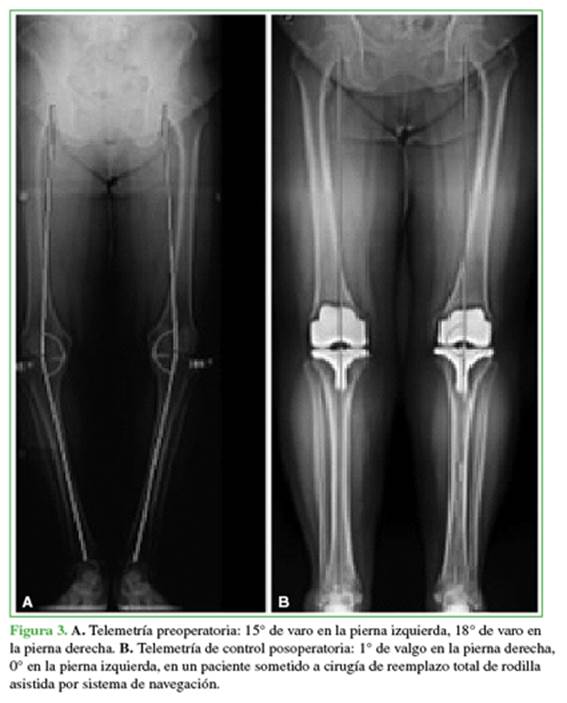

En este estudio, los RTR primarios guiados por sistema de navegación fueron más precisos para lograr la alineación final del miembro en un eje mecánico de 0° ± 3° (Figura 3) en comparación con el RTR mediante técnica convencional (Figura 4).

El 14% del grupo A tenía un IMC >35 kg/m2 y, en el grupo B, fue superior, pero la diferencia no fue significativa. En cuanto al eje del miembro obtenido por telemetría posoperatoria, expresado en grados, fue de 1° y 3° en la mayoría del grupo con prótesis navegada (70%) y de 0° en el 18%. En el grupo B, estos porcentajes fueron menores: 1-3° (46%), 0° (3%) y 6° o más (21%), con una diferencia estadísticamente significativa (Figuras 1 y 2). En lo que respecta a la desviación del eje en varo y en valgo, las cirugías con sistema de navegación arrojaron un resultado del 10% en valgo (L) y aquellas con técnica convencional, del 19%. El resto de los pacientes tenía un eje posoperatorio en varo (R).